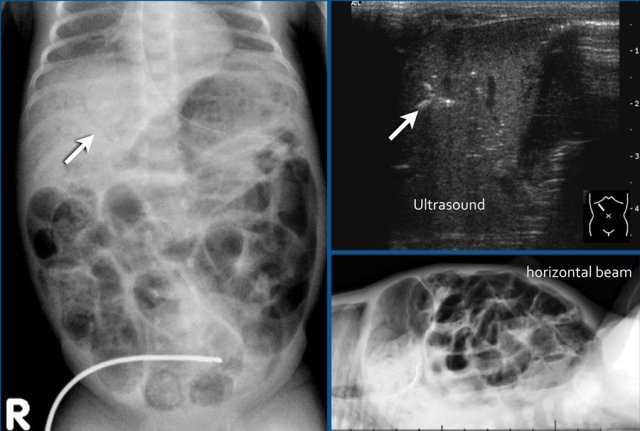

The images show a typical case of NEC with pneumatosis intestinalis.

On the horizontal beam image there is no sign of free air.

Here images of a neonate who developed NEC.

At this early stage the radiograph only shows non-specific bowel dilatation.

At this stage you cannot make the diagnosis.